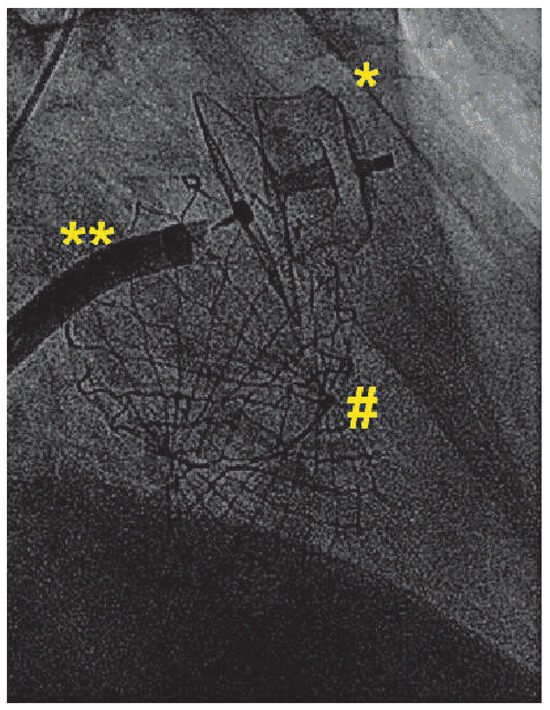

Valve implantation was followed by transseptal puncture through a right femoral venous access using an 8French Mullins transseptal sheath and the Brockenbrough Curved Needle (Medtronic, Minneapolis, USA). Using contrast injections through the transseptal sheath, the left atrial appendage (LAA) was visualised and a thrombus within the left atrial appendage was not detected. The transseptal sheath was replaced by the Amplatzer TorqueVue 45×45 sheath (St. Jude Medical, St. Paul, USA). Sizing of the left atrial appendage was performed using the outer diameter of the delivery sheath as a reference (14F; 5.4 mm; Figure 1). An Amplatzer Amulet 28 mm LAA-Occluder (St. Jude Medical, St. Paul, USA) was deployed in the left atrial appendage in a stable position with good sealing (Figure 2).

The following day, a transthoracic echocardiography confirmed a well-functioning CoreValve prosthesis with only trivial paravalvular regurgitation and a mean transvalvular gradient of 5 mm Hg as well as the correct position of the Amplatzer Amulet 28-mm Occluder.

Figure 2. Combined interventions: Combined transcatheter aortic valve replacement and left atrial appendage occlusion. (*) Amplatzer Amulet 28 mm; (**) Amplatzer TorqueVue Sheath 14F; (#) CoreValve 31 mm.